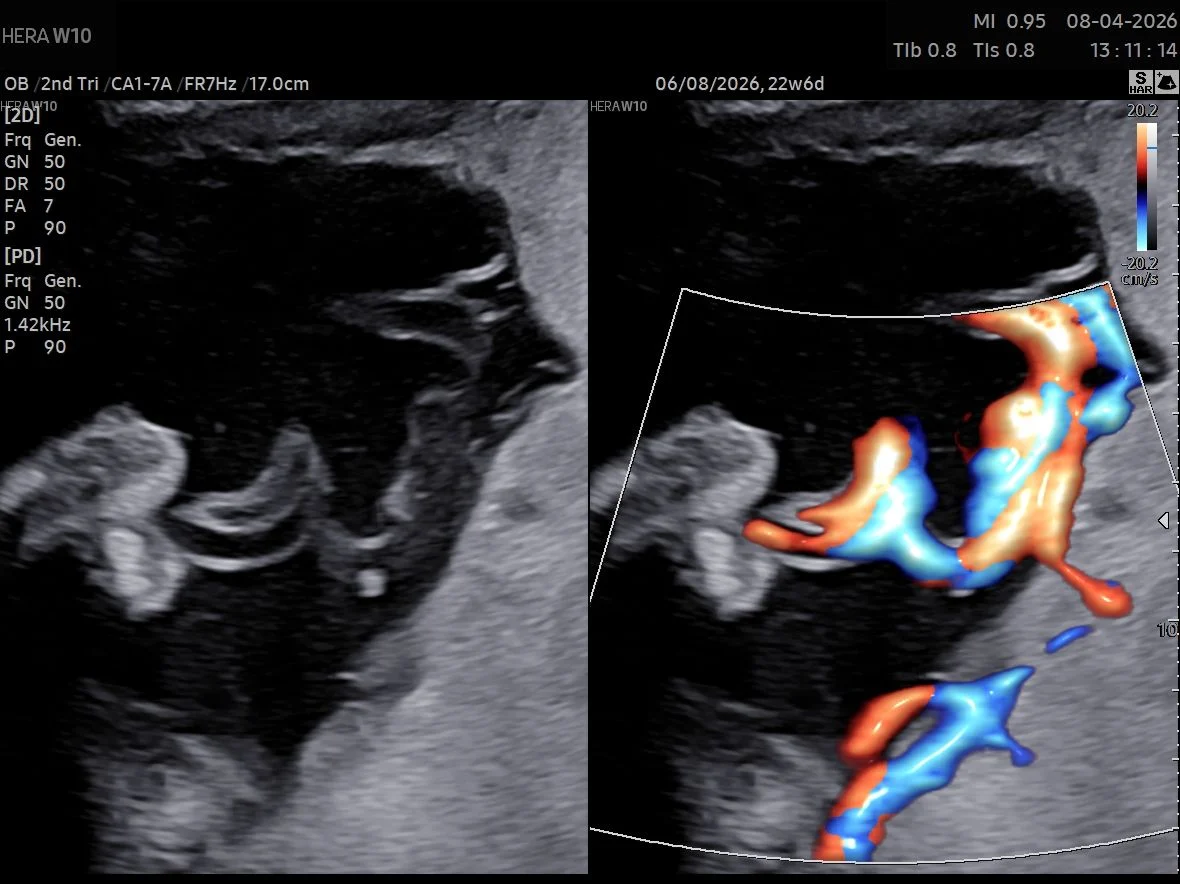

“Proximal cord insertion in MC twins

Proximal cord insertion (PCI) in Monochorionic twins is defined as cord to cord distance ≤ 4cm. It occurs in approximately 3-5% of MC pregnancies. it’s more common in MCMA twins.

Below is a a case of MCMA twins with PCI. Note also the large AA anastomoses between both cords with characteristic bidirectional blood flow.”